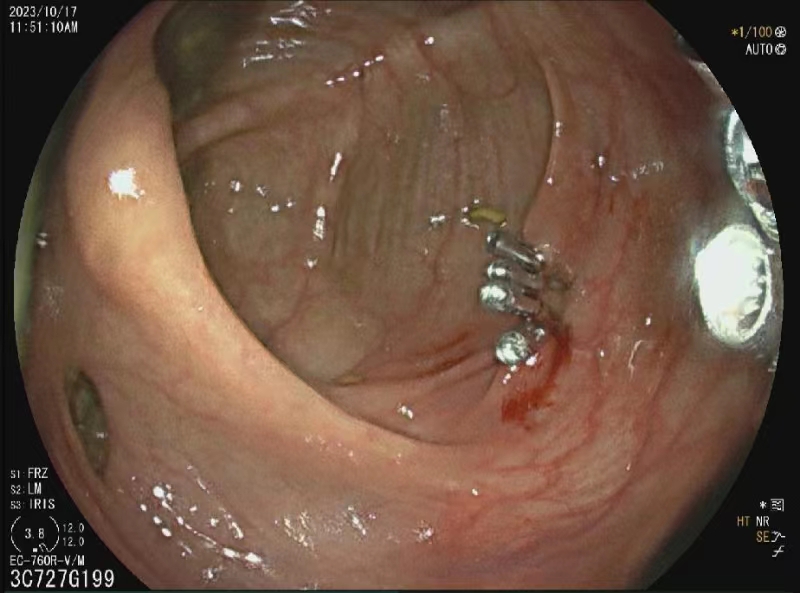

为方便广大人民群众咨询就诊,彝良县人民医院消化内科增设消化内科胃肠镜门诊。胃肠镜门诊于2023年12月顺利开诊。消化内科胃肠镜门诊将会帮助患者方便、快捷、及时完成胃肠镜检查、完成早癌筛查,远离胃肠道疾病。同时提供胃肠镜咨询、预约、检查、检查结果判读、评估手术风险及可行性,解读胃肠镜标本病理报告,为胃肠道疾病患者提供综合性治疗方案。为术后患者制定随访计划并追踪随访。对不明白胃肠镜检查注意事项的患者,特别是不明白肠镜检查前准备事项及肠道清洁药物服用方法的患者提供指导。 诊疗范围 1. 胃肠镜检查咨询、预约、检查; 2. 胃肠镜检查结果及病理结果分析、判读; 3. 胃肠镜下治疗评估及制定治疗方案; 4. 胃肠镜下早癌筛查,消化道出血、息肉、肿瘤的诊断及治疗; 5. 胃肠镜治疗后随访; 6. 幽门螺旋杆菌感染诊断及治疗。 坐诊时间 周三:上午08:00-11:30 ,下午14:30-17:30 周五:上午08:00-11:30 ,下午14:30-17:30 EMR术 结肠 欢迎关注“彝良县人民医院微信公众号”,方便您就医(提供预约挂号、缴费、检验检查报告查询、住院清单查询等服务)。 供稿:田应香、代堂伟 编辑:李 菲 审核:龙 海